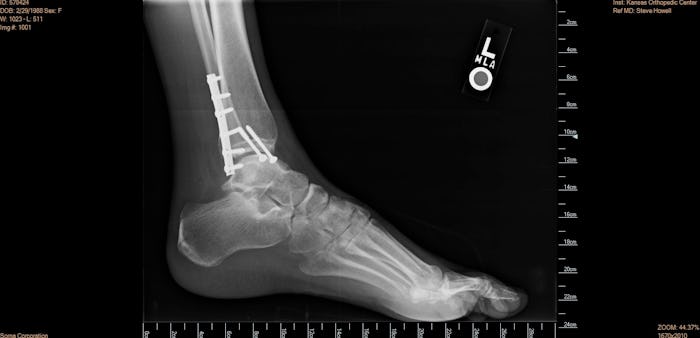

Just because you’re pregnant doesn’t mean that you stop living life, being you, and dealing with potential health issues. There may be situations that arise during the course of your pregnancy that require you to need to get an X-ray. Maybe you fell and broke your arm, or maybe you have something else going on and your care provider wants to take an X-ray to get a better look. There are plenty of reasons that you might need to expose yourself to X-ray machines while carrying a baby, so it’s a good idea to know if it’s OK.

Both sources seem to agree that X-rays on teeth, arms, legs, feet, or any other extremities are safe due to the low levels of radiation involved and the fact that these body parts are far enough away from your uterus (and therefore your fetus) to cause any harm. If you’re getting an abdominal or trunk X-ray, you should be more cautious. Of course, regardless of what part of your body you’re having X-rayed, you should always tell your doctor ahead of time if you’re pregnant.